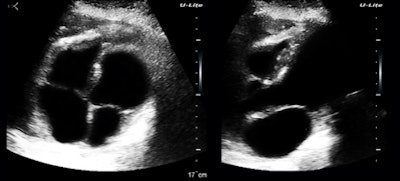

What is really interesting is that with a physician user, there are about a zillion daily uses for ultraportable ultrasound within hospitals. I interviewed and became friends with Dr. Nicolas Thiounn when I was in Paris recently. He is a professor of urology who has gotten a lot of attention for pioneering partial nephrectomy and superselective intraprostatic cancer treatment. He has been very happy with his U-Lite, which he started using to identify or exclude hydronephrosis in referred patients. Now, he uses the U-Lite as an integral part of his physical examination of office and hospitalized patients.

This is a strength of radiology and one that we share uniquely with pathology. This particular example was easy, because the diagnosis is just a descriptive term, but we're not always as lucky. The clinic population has a high prevalence of cholelithiasis, obesity, hypertension, and metabolic syndrome (figure 3).

There are two reasons why I am using up limited image real estate here with something as pedestrian seeming as a fatty pancreas. The diagnostic issue is not identifying obesity but in assessing cardiac and insulin resistance risks. Like fatty liver, pancreatic fat is a visceral fat deposition a big step closer to metabolic syndrome. The second is that the U-Lite does a much better job in the presence of obesity than I would have anticipated. Maybe this has to do with the submillimeter range gating?